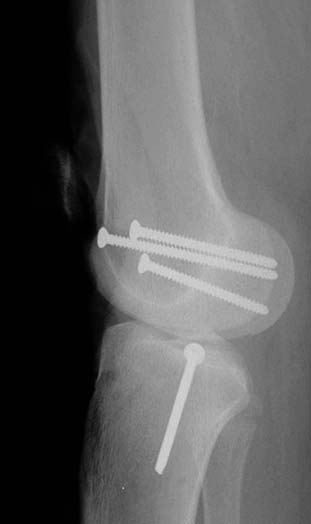

“Перелом наружного мыщелка правого бедра во фрональной плоскости был не замечен”

При изолированных переломах можно лечить миниинвазивно каннюлированными винтами, но в большинстве Hoffa компонент сопровождается другими типами перелома дистального бедра. Выбор доступа зависит от расположения фрагментов и большинстве латеральный субвастус доступ подойдет для фиксации перелома.

В данном случае предпочтителен парапателлярный доступ, где необходимо создать лучший обзор к мыщелку. После остеотомии и репозиции фиксацию надо проделать поперечными винтами и дополнительно задней antiglade plate - сделанной из 1/3 tubular plate.

Здесь представлены различные варианты фиксации перелома, а также снимки комбинации перелома с повреждением хряща (12-19). Пластика хряща OsseoFit и установка custom made plate.

Спасибо большое за советы! Добавляю некоторые КТ снимки. Перелом коллеги не диагностировали, видимо, расценив костную травму как повреждение задне-латерального комплекса коленного сустава. Отпишусь по результату выполненной операции.

Остеосинтез LCP пластиной